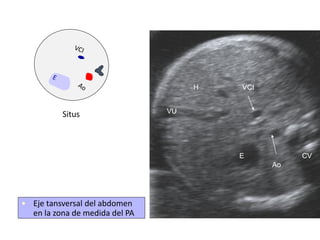

• Eje tansversal del abdomen

en la zona de medida del PA

Situs

Ao

VCI

E CV

H

VU

⚫ Ao por delante y

lado izquierdo de la

columna vertebral

⚫ VCI más adelantada

y hacia la derecha

⚫ Diámetro de la VCI

no superior al de la

⚫ Estómago en el lado

izquierdo

⚫ Comprobar la

presencia de ductus

venoso

Abdomen